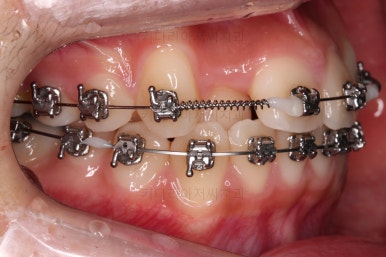

약간의 뻗침과 아랫니에 비해 아주 약간 나와있는 앞니를 말씀하셨기 때문에 가능한 방법을 제시하고 치료를 이어갑니다.

입시로 해둔 치아는 잘 버티고 있네요.

보통 뒤로 당겨야 할 양이 많다면 미니스크류를 사용하는데, 이번 환자분은 그정도 까지는 아니어서 최대한 철사 자체에 힘을 주고 뺐다꼈다 하는 고무줄을 사용하며 치료를 마무리하기로 했어요.